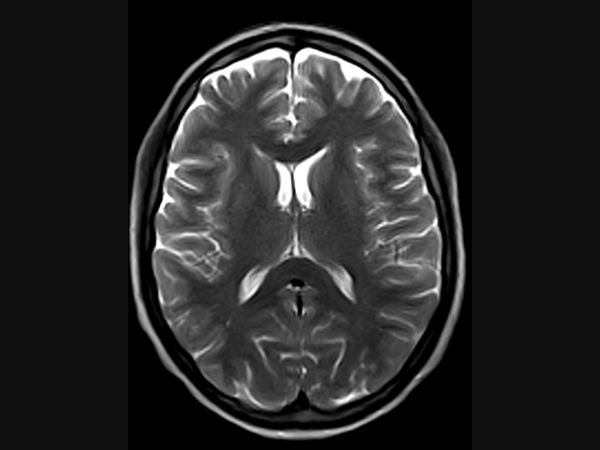

Klinické snímky